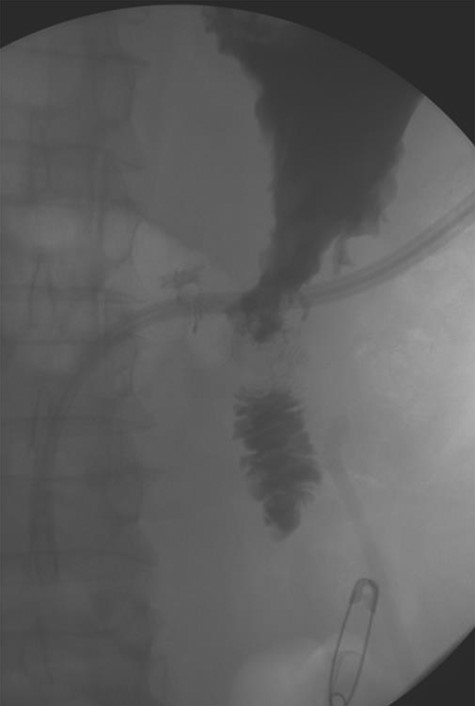

A 56-year-old African American male presented in 2015 with abdominal pain, with associated melena and hematochezia. The patient has a history of chronic back pain for which he takes 600 mg ibuprofen daily, alcohol abuse, tobacco use and a previous GI bleed in 2011, which necessitated 6 units (U) of packed red blood cells (PRBCs) and emergency therapeutic endoscopy. The patient was found to be hypotensive to 76/56 mm Hg, and hemoglobin (Hgb) was found to be 9.4 g/dl, from a previous baseline of 10.6 g/dl. His rectal examination was guaiac positive. A repeat Hgb was found to be 6.5 g/dl. The patient was given 3 U of PRBC and an emergency endoscopy was performed. On endoscopy, the patient was found to have a 6 cm gastric ulcer with an associated vessel underneath of a large clot. Due to the high risk nature of the bleed, it was felt by the gastroenterologist that the patient should undergo an endovascular angioembolization (Fig. 1). The patient was brought to the Interventional Radiology Suite for the procedure. The patient’s right common femoral artery was accessed and the celiac trunk was selected. A subselective common hepatic arteriogram was performed, which demonstrated active extravasation arising from the proximal aspect of the GDA. The GDA was then coil embolized both proximal and distal to the site of bleeding using five microcoils. Repeat arteriogram demonstrated no further opacification of the GDA and no further extravasation (Fig. 2).

Demonstrating active extravasation of the GDA during a subselective GDA arteriogram